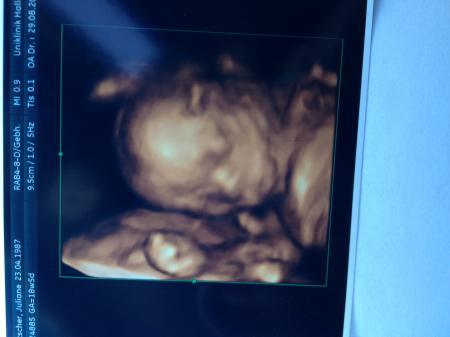

Ich versuche mal noch das US-Bild von Freitag hochzuladen :)